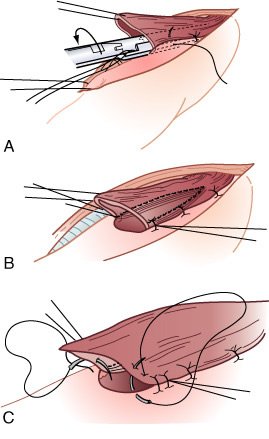

O grampeador é fechado, com aproximação das pás; mas, antes de dispará-lo, realizam-se dois pontos de suspensão em cada lado, entre o estômago anterior e o esôfago adjacente. B, Quando a lâmina do grampeador é avançada, a "parede comum" entre o esôfago e o estômago é seccionada, criando-se uma anastomose ipsilateral de 3 cm de extensão. Então, a sutura dos ângulos é feita em cada lado da gastrotomia. C, A gastroto-mia e o esôfago aberto remanescente são aproximados em duas camadas

O estômago é mobilizado através do mediastino posterior no leito esofagico original e anastomosado (manual ou por grampeamento) ao esôfago cervical.